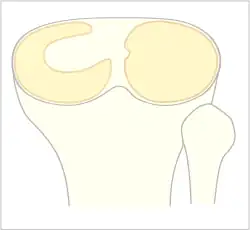

Ménisque discoïde

Le ménisque normal a une forme de croissant fin. Dans le cas du ménisque discoïde il existe un épaississement du ménisque pouvant aller d'une forme en croissant épais jusqu'à une forme de disque recouvrant le plateau tibial.

La classification de Watanabe décrit trois types de ménisque discoïde selon le degré de couverture du plateau tibial et selon l'attache postérieure du ménisque : ménisque discoïde complet, incomplet et variant-ligament de Wrisberg[1],[2].

Le ménisque discoïde complet recouvre totalement le plateau tibial externe (type I)[2]. Le ménisque discoïde incomplet (type II) ne le recouvre qu'incomplètement[2]. Dans le cas du variant-ligament de Wrisberg, il n'existe pas de frein méniscal postérieur[2].